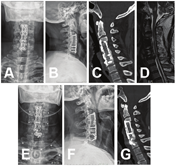

对于病变≥2节段ASD的5例患者采用后路颈椎单开门椎管扩大成形术。麻醉满意后,患者取俯卧位,Mayfield头架固定颈椎于轻度屈曲位。于颈后正中沿枕骨粗隆至C7连线做切口,切口长度根据需要开门的椎板数量及位置确定,常规行C3~7开门减压。沿颈后正中项韧带作锐性分离,显露出C2~T1棘突及双侧椎板、侧块。用磨钻于双侧椎板与侧块交界开槽,常规以右侧为门轴,咬除C2/3、C7~T1间黄韧带后,将椎板向右侧掀起,于每一椎板处安置1枚微型钢板,并用2~4枚螺钉固定牢固(图2)。